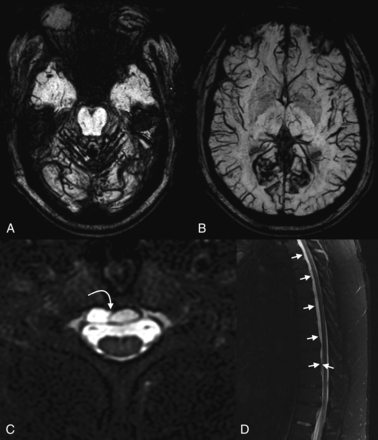

There have been several reports of SIH presenting with or coinciding with the presence of SS (Fig 8).87⇓-89 One review of patients with SS noted a spinal extradural fluid collection in approximately 50% of patients.13 While SS is not reversible, repair of the inciting dural defect, often found via a dynamic CT myelogram, may prevent further bleeding and lead to stability or improvement of symptoms.90,91

SIH presenting as superficial siderosis. A 37-year-old man who presented with episodes of dizziness and loss of consciousness was found to have diffuse posterior fossa–predominant superficial siderosis on axial SWI (A and B). Subsequent imaging of the spine demonstrated a ventral extradural fluid collection (curved arrow, C; straight arrows, D). A subsequent hyperdynamic CT myelogram identified the source of the CSF leak, which was surgically repaired.